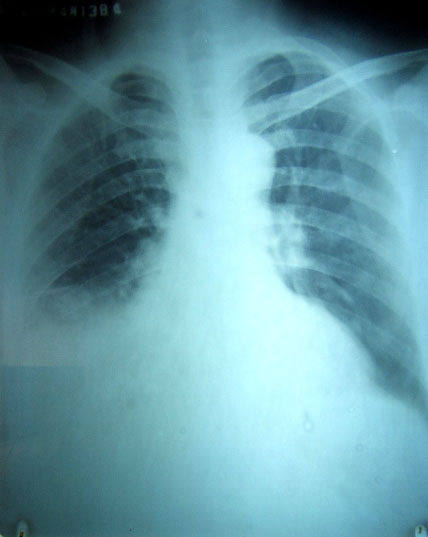

以下是引用software在2007-5-18 19:48:00的发言:[br]患者男,因发热,咳嗽,咳痰半月余而入院,有盗汗,双手会不自主的颤抖。 [br][br]这是第一张片:[br][br]明摆着是胸腔积液,还有胸膜肥厚,入院后行胸穿,抽出淡褐色胸水,生化检查,我只记得糖0.8,其它的不记得了,李凡他(+)。 [br][br]第二天复查胸片,就成这模样了。。。。。 [br]